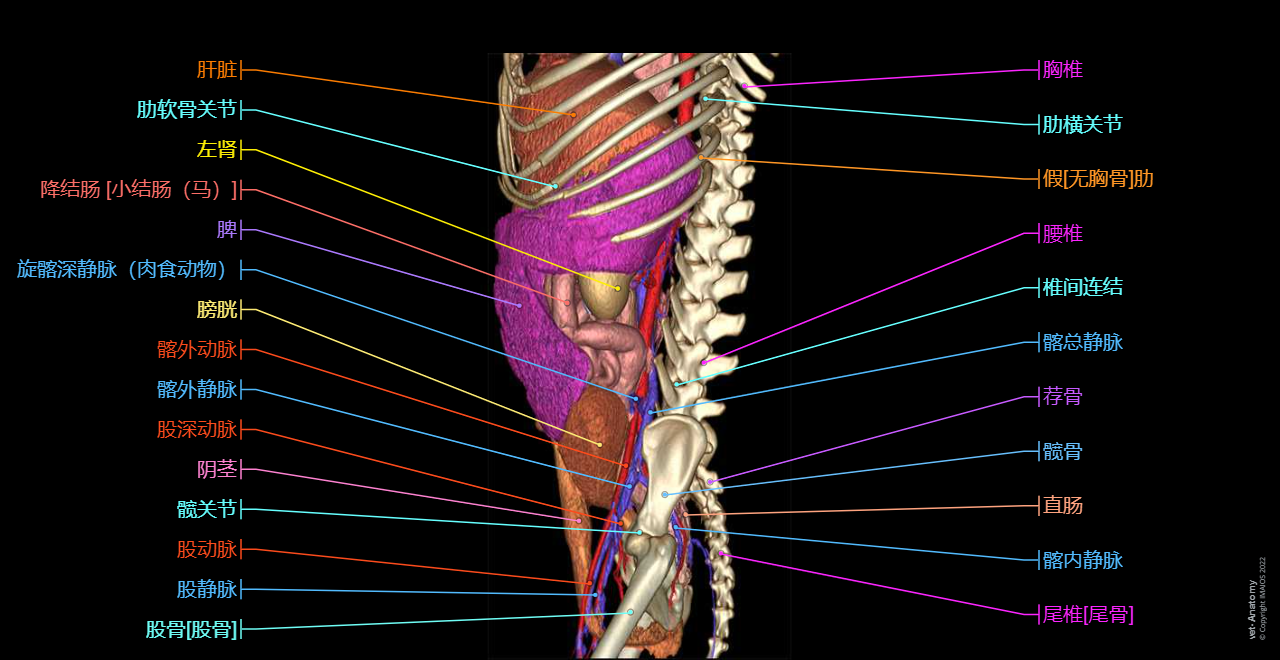

vet-Anatomy兽医图集的本模块是关于CT扫描的犬类腹部和骨盆。

CT图像来自一只健康的6岁阉割雄性犬。

在vet-Anatomy动物图集的此模块中,计算机断层扫描(CT)显示了标有解剖结构的犬科腹腔和骨盆横截面,并用3D图像显示犬科腹部。

CT图像存在3个平面方向(横向,矢状和背侧),并且使用两种对照方式(软组织/血管和骨骼)展现。本模块的末尾提供其他3D解剖图像,便于进一步了解犬科总体解剖结构,展示了骨骼、内脏(肝脏、脾脏、胰腺、消化道)、泌尿生殖系统、动脉、全身静脉系统(主要是尾腔静脉及其分支)、门静脉系统、肌肉和表面解剖的三维容积透视图。

毕业于欧洲兽医诊断影像学学会的Susanne AEB Boroffka博士(荷兰乌得勒支)对健康的6岁雄性阉割犬(拉布拉多猎犬)注射碘化造影剂并完成计算机断层扫描。

三维容积透视图是由Antoine Micheau博士在GE ADW上使用相同的CT医学影像成像数据而创建。

放射科医生(法国蒙彼利埃)Antoine Micheau博士和放射科医生(法国蒙彼利埃)Denis Hoa博士完成了图像显示、解剖标记和解剖释义工作。